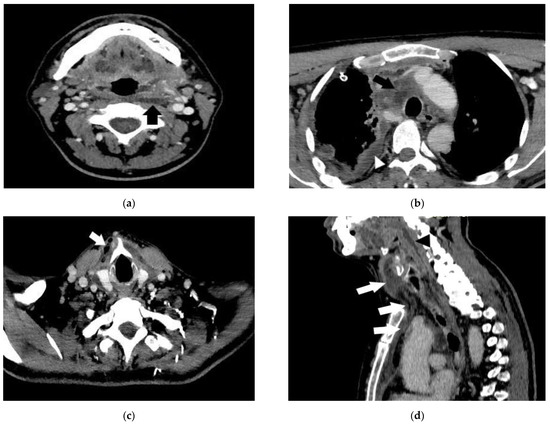

- Case 4.